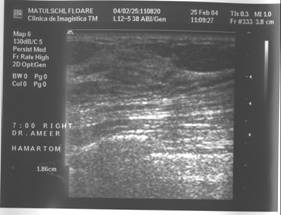

HAMARTOM